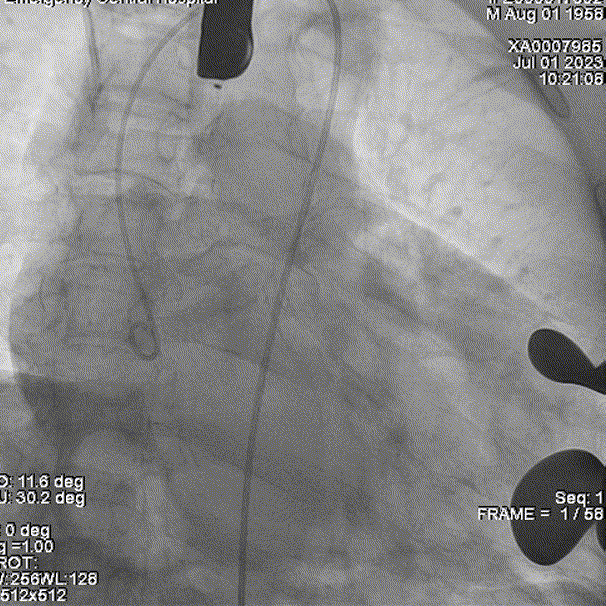

猪尾导管置于右冠窦行根部造影(右冠窦向右侧转位):

穿刺置入导丝,建立轨道。定位件进入对应窦部:

将瓣膜件降至瓣环平面,造影下定位:

释放J-valve29#瓣膜:

复查根部造影,未见明显反流,瓣膜形态和位置满意,双侧冠脉显影良好: